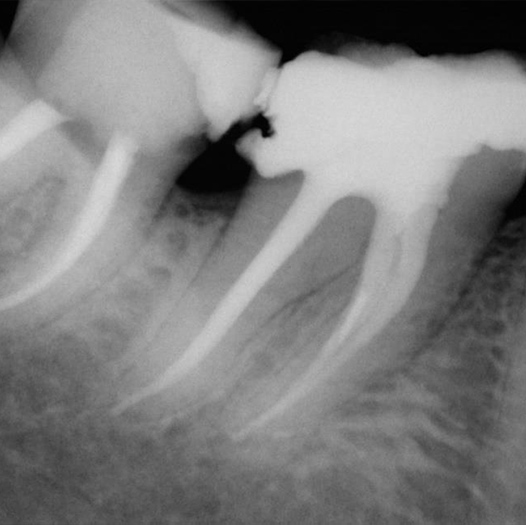

Before

Before Root Canal treatment